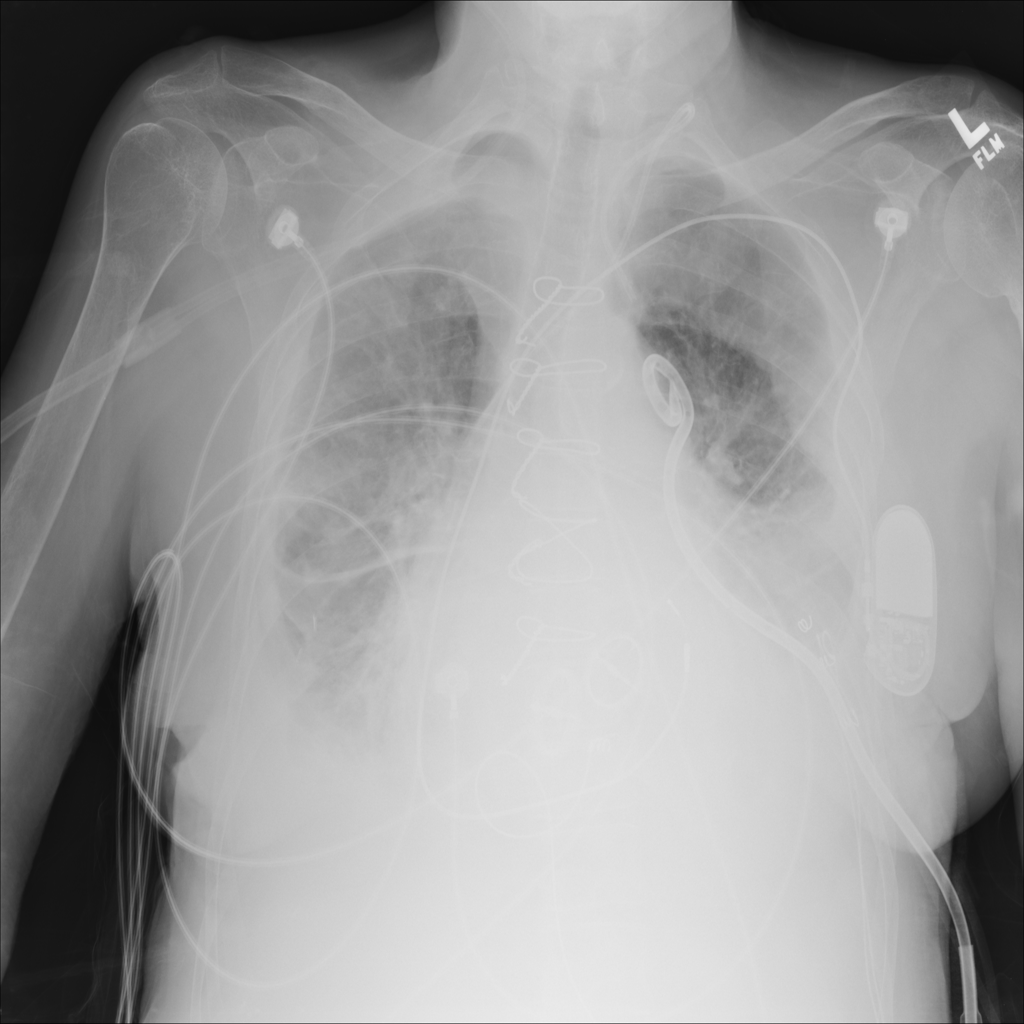

PAT-86C8 · IMG-000Effusion

PAT-86C8 · IMG-000

PA